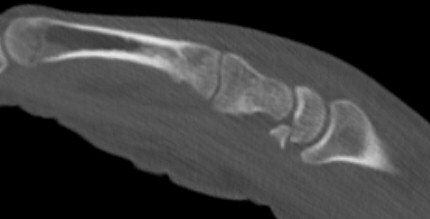

Skada: Fraktur lunatum

Fraktur i volara polen efter högenergitrauma

- Utred med DT